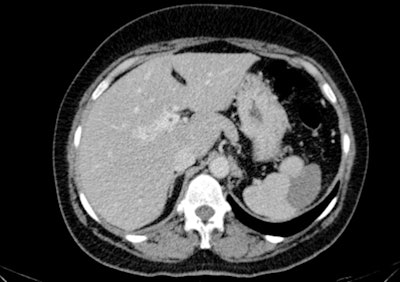

Caudate lobe hypertrophy in a patient with portal cavernoma. If suspected, a follow-up CT may be done to change the association between the rib/diaphragm and adjacent liver at a different inspiration level or with the patient in a decubitus position. All images courtesy of Drs. A.V. Neagu and C.-I. Betianu, originally presented at ECR 2020.

Caudate lobe hypertrophy in a patient with portal cavernoma. If suspected, a follow-up CT may be done to change the association between the rib/diaphragm and adjacent liver at a different inspiration level or with the patient in a decubitus position. All images courtesy of Drs. A.V. Neagu and C.-I. Betianu, originally presented at ECR 2020.Pseudolesions tend to have a typical appearance, but there are many cases with atypical patterns, explained Neagu and Betianu, who received a cum laude award from the ECR 2020 e-poster judges.